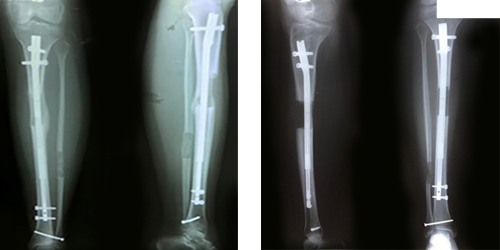

Lengthening using self-extending intramedullary screws

Prof. Al-Sayyad Center is one of the pioneers in cosmetic orthopedic lengthening surgery and bone lengthening with internal self-elongating screws. Our extensions started in June 2002

The use of the spinal screw technique began in 2008, three years before the use of this technique in the United States of America.

The initial use was with the pioneering German Lift Bonn device, and hundreds of operations have been performed with this technology, in addition to

Using the distinguished Precise 2 screw, both of which work with remote control.

For the turn-bond, it works with an internal electric field and an internal motor with the screw, and the Presize 2 works by using a large-sized external magnet technology in a unit called (ERC) to move a magnet inside the screw that leads to the lengthening of the screw through this magnetic interaction.

It is used to compensate for the length of the shin bone, thigh and humerus.